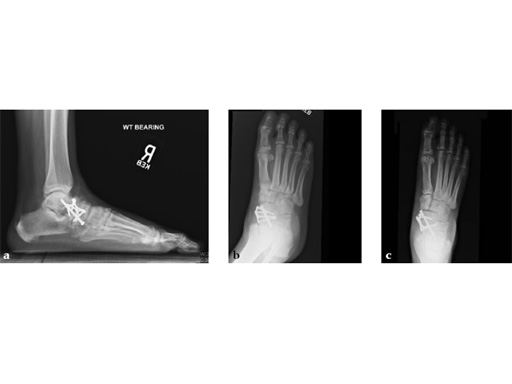

Case 4: First TMT fusion plate

A 60-year-old woman with pes plano abductovalgus (flatfoot deformity).

Case provided by Andrew Sands, New York, New York, USA

The patient was treated by headless compression screw 6.5 tuber osteotomy, TMT plantarflexing osteotomy, and first TMT fusion a plate.